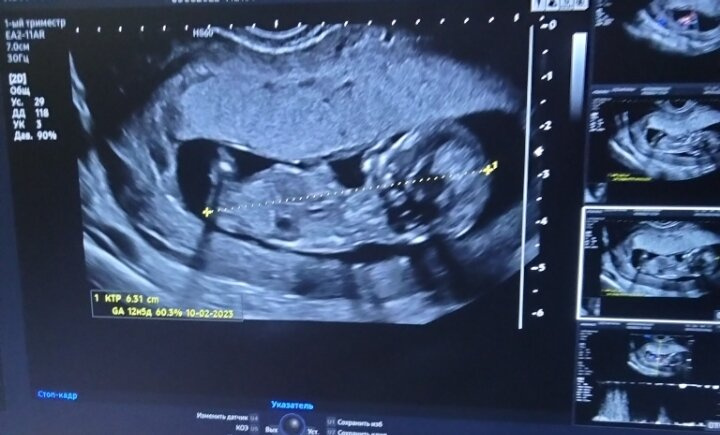

Все хорошо, все в норме?врач сказала, что красавчик

Заходила я в кабинет УЗИ 4 раза, никак не могли растормошить?уже и поела и походила, еле еле повернулся, но всё-таки дал на себя посмотреть.

Предположительно мальчик, но я так и чувствовала, что мальчик?

Все, этот этап почти прошли, осталось дождаться крови и растем дальше❤️